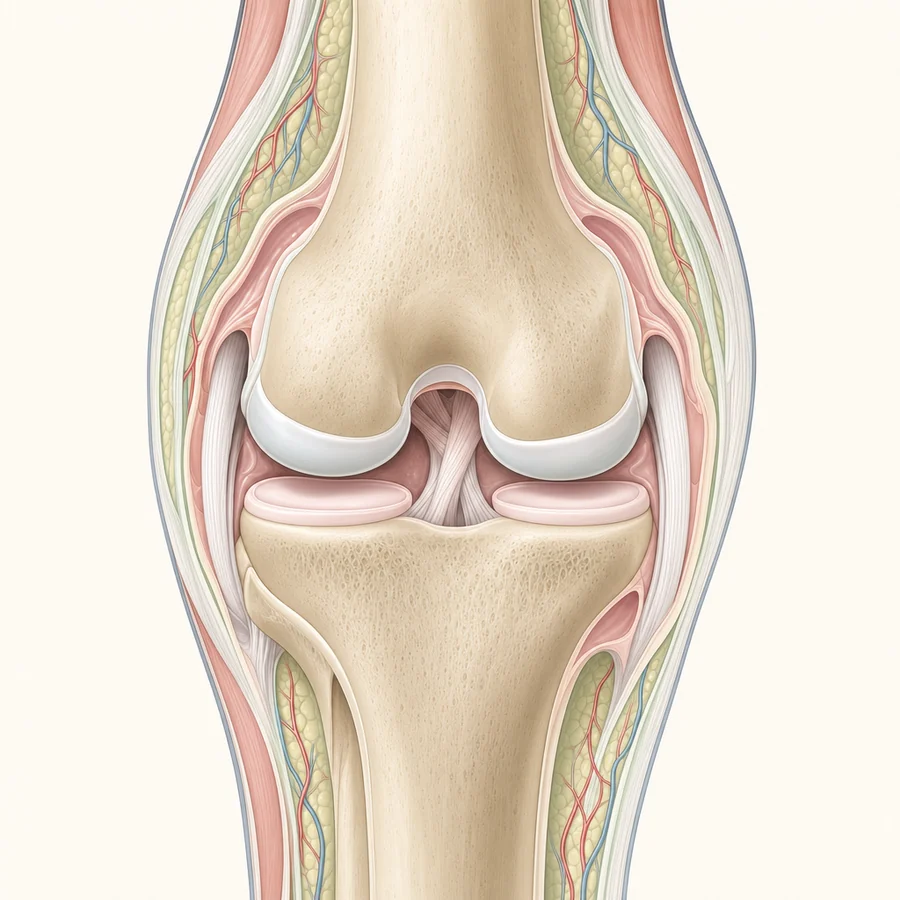

GAE for Knee Pain

Knee-targeted embolization

Genicular Artery Embolization (GAE) treats knee osteoarthritis pain without surgery. Step through the process or watch the video.

In a knee with osteoarthritis, the inflamed joint lining (the synovium) grows extra, abnormal blood vessels. That excess blood flow feeds ongoing inflammation, which is a major driver of knee pain.